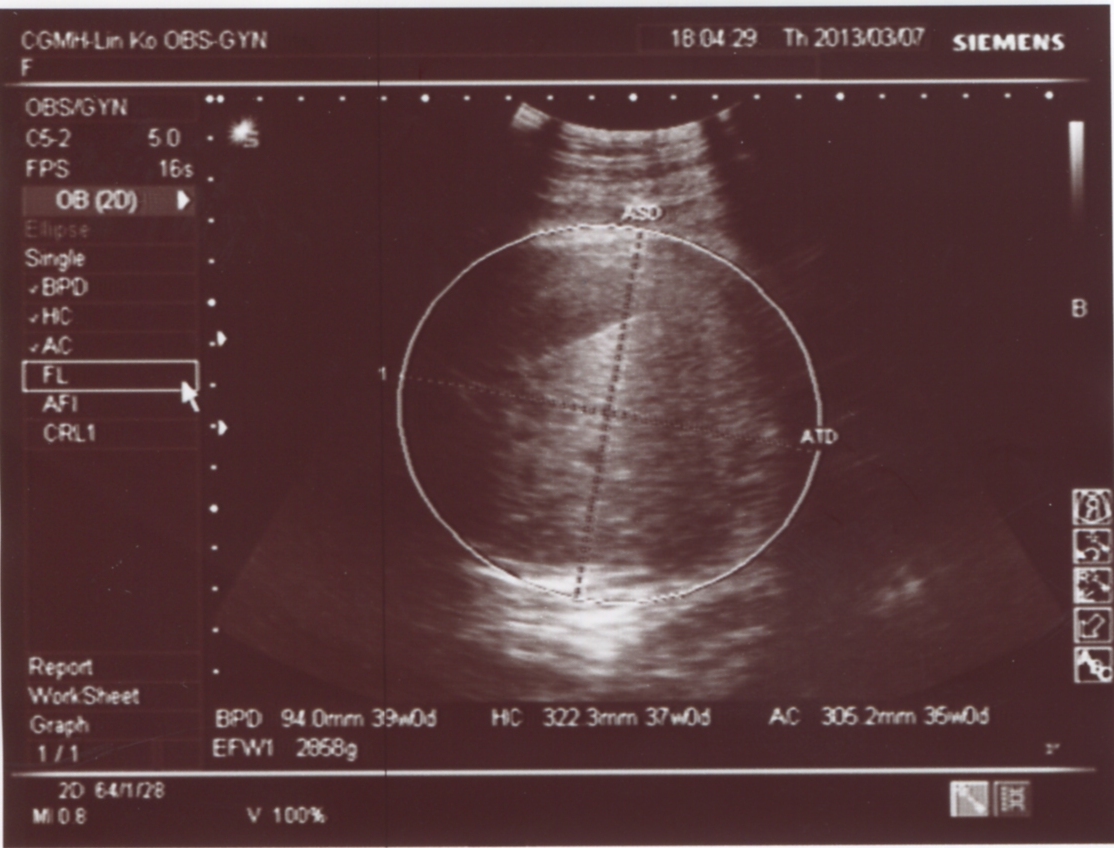

寶寶這次多增加了444g,體重來到2868g(醫生說有點大,不過沒關係)

大頭寶寶Bepo的頭還是依舊的大,但頭來到39週!!!醫生講了一句:這孩子就是頭大!!胎頭已下降到骨盆腔囉~

肚圍37週,腿長36週